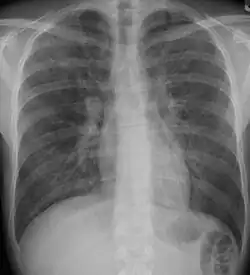

Pneumocystis pneumonia can present with interstitial lung disease, as seen in the reticular markings on this AP chest x-ray.

A chest X-ray demonstrating pulmonary fibrosis due to amiodarone

Diagnosis of ILD involves assessing the signs and symptoms as well as a detailed history investigating occupational exposures. ILD usually presents with dyspnea, worsening exercise intolerance and 30-50% of those with ILD have a chronic cough. On examination, velcro crackles, in which the crackles compare to the sound of velcro being unfastened, are common in ILD.[10] Pulmonary function tests usually show a restrictive defect with decreased diffusion capacity of carbon monoxide (DLCO) indicating reduced alveolar to blood capillary transport.[10] Pulmonary function testing is indicated for all people with ILD and the FVC loss and DLCO is prognostic, with an FVC loss of greater than 5% per year associated with a poor prognosis in fibrosis subtypes of ILD.[10]

A chest x-ray is 63% sensitive and 93% specific for ILD.[10] With advances in computed tomography, CT scans of the chest have supplanted lung biopsy as the preferred diagnostic test for ILD. A thoracic CT scan is 91% sensitive and 71% specific for ILD.[10] In higher income countries, less than 10% of people with ILD undergo a lung biopsy as part of the diagnostic evaluation.[16]